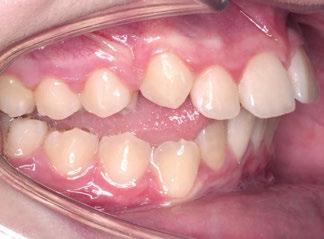

La exploración intraoral (figuras 4 a 8) revela una Clase II molar y canina completa, líneas 1/2 dentarias superior 0,5 mm e inferior 1 mm ambas desviadas hacia la derecha, los incisivos superiores excesivamente protruidos y vestibulizados (seguramente debido a la interposición del labio inferior), resalte de 13 mm y sobremordida 2/3 de corona. La discrepancia oseodentaria

inferior es de -3,5 mm y la curva de Spee de 4 mm.